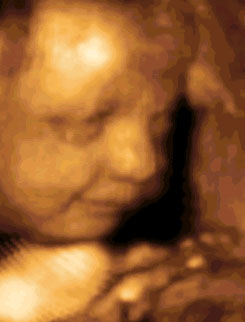

Alla ventunesima settimana di gravidanza la pancia comincia a vedersi bene ed è possibile sentire distintamente i movimenti del piccolo.  ...